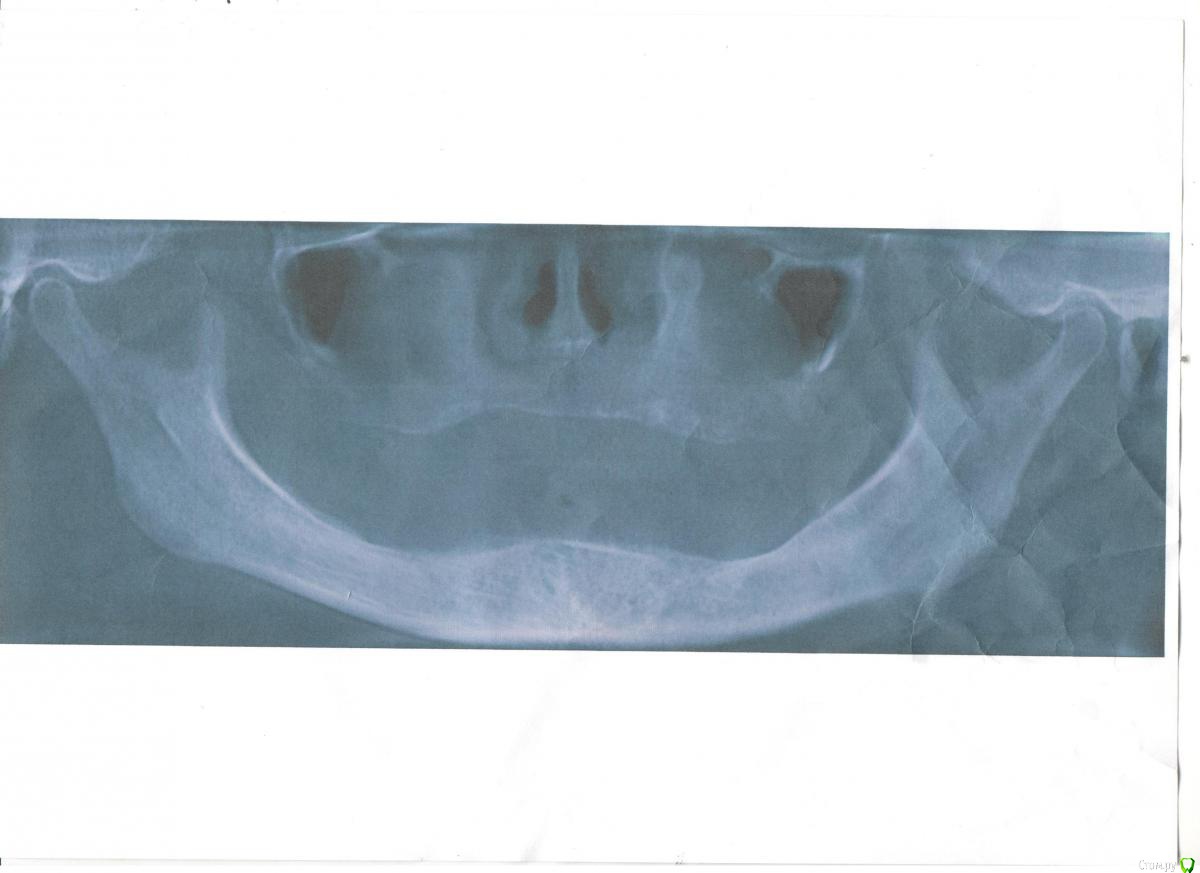

Татьяна Luckyman Опубликовано 21 июня, 2017 Поделиться Опубликовано 21 июня, 2017 Здравствуйте! Заранее извиняюсь, если будет неверная терминология, все описание со слов мамы.Итак, она около 10 лет ходит со съемными протезами (своих зубов не осталось вообще), очень сильно съеден низ, десна тонкая и атрофированная. По словам врача нужно как можно быстрее ставить импланты, иначе в ближайший год мама может остаться вообще без зубов, ибо не на что будет ставить.В одной клинике советуют ставить хотя бы низ, но лучше сразу и верх, по 4 импланта, мост, балку, ценник примерно 400 тысяч за верх и низ, если только низ 206, кажется.В другом месте предлагают делать пока только низ: всего 2 импланта, также балку, ценник 150 тысяч. Вопросы такие: 1. Как делать лучше? Есть ли еще варианты, которые помогут сохранить зубы?2. Сколько в действительности еще есть времени на раздумья, подготовку и, в конце концов, накопление средств?3. Выделяются ли квоты на такие операции? Хотелось бы сделать сразу и верх и низ, часть суммы накоплена, но вряд ли остальное успеем собрать за полгода.4. Импланты чьего производства лучше ставить, а на какие вообще не соглашаться? Ссылка на комментарий

red_butler Опубликовано 21 июня, 2017 Поделиться Опубликовано 21 июня, 2017 1. Как делать лучше? Лучше не бывает, каждый вариант имеет плюсы и минусы. Есть ли еще варианты, которые помогут сохранить зубы? о каких зубах речь??? На снимках зубы отсутствуют 4. Импланты чьего производства лучше ставить, а на какие вообще не соглашаться? Ищите врача, а не импланты. Ссылка на комментарий